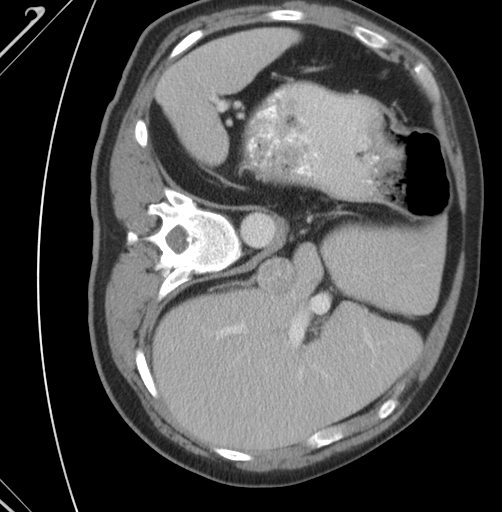

![]() |

| Input | GT | 2D | 3D | HResFormer (Ours) |

Effectiveness of each component of our HResFormer. Table VI shows the effectiveness of our HResFormer from the following aspects: (1) Pure 2D-based and 3D-based network. Compared to the state-of-the-arts, we can see that our 2D model and 3D model achieve slightly lower results with 81.05% vs. 81.96% (Huang et al., 2021) for 2D and 85.39% vs. 86.57% (Zhou et al., 2023) for 3D. The comparison shows that the effectiveness of our HResFormer is not due to the strong backbones in pure 2D and 3D models. (2) Effectiveness of HGLM. Table VI shows that our HGLM can enhance the model performance from 87.23% to 88.21%, demonstrating the effective design of HGLM in fusing the mutual information between 2D and 3D network. (3) Effectiveness of residual learning. With residual learning, we can see that the performance consistently improves from 88.21% and 89.10%, showing that residual learning can further enhance the segmentation results generated by the 3D model. The design of residual learning of HResFormer can effectively leverage the fine-grained inner-slice information learned by the 2D network and intra-slice information generated by the 3D network. Figure 3 visualizes the segmentation results of the 2D and 3D parts of HResFormer, where we can see that our HResFormer can effectively enhance the performance.